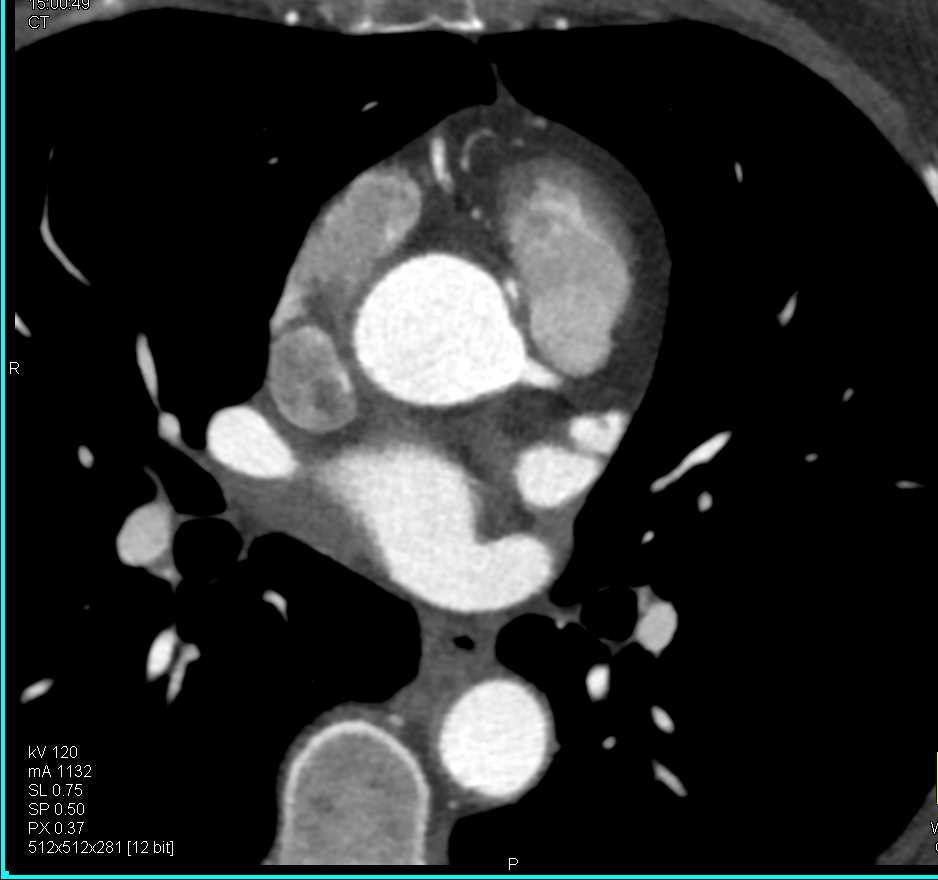

Left Ventricular Aneurysm